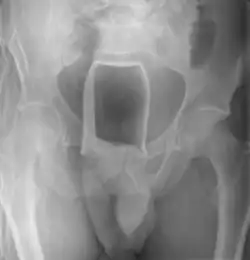

Обычно делают несколько рентгеновских снимков, чтобы точно определить место нахождения инородного тела. Инородные тела из малоконтрастного материала (например, пластика) могут потребовать ультразвукового исследования или компьютерной томографии.[28] Магнитно-резонансная томография противопоказана, особенно если неизвестен материал инородного тела. Инородные тела прямой кишки могут проникать глубоко в толстую кишку, при определённых обстоятельствах вплоть до правого изгиба ободочной кишки.[9]